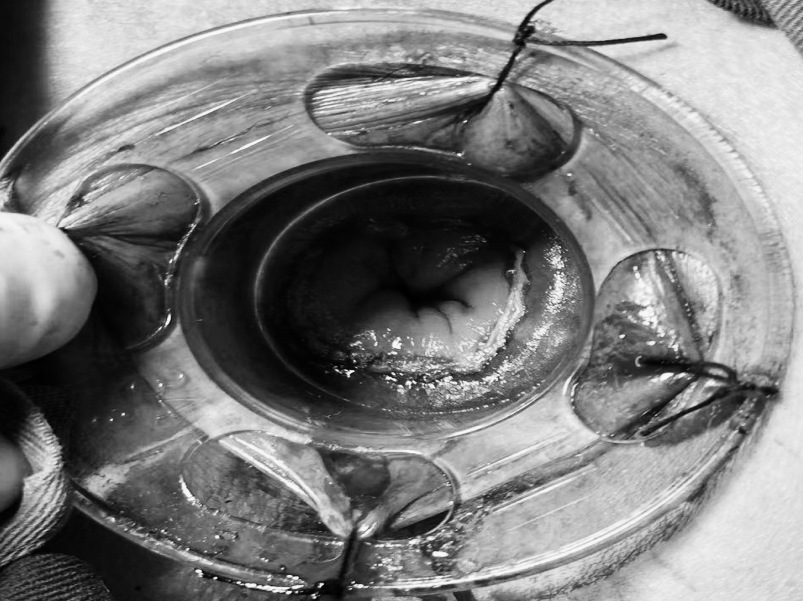

多年来,贵州航天医院各科室紧跟医学前沿,不断强技术、补短板,大力开展新技术、新项目,完成了许多高精尖、高难度、本地区“首例”的技术,填补了医院医疗技术空白,满足了群众日益增长的医疗需求。 本期,我们将为大家带来普外科特色技术——腹腔镜下腹股沟疝无张力修补术(TAPP)。 案例分享 患者在两年前检查发现双侧腹股沟区可复性包块,因当时症状较轻,偶有疼痛,患者未予重视,最近几个月,疼痛愈发频繁,严重影响了工作和生活,故前来我院普外科就诊。科室为患者完善了超声等相关检查后,明确诊断为:双侧腹股沟疝。 在充分与患者进行沟通同意后,制定并成功实施了腹腔镜下腹股沟疝无张力修补术治疗的方案,术中出血量少,术后第三天顺利出院。 腹腔镜下腹股沟疝无张力修补术(TAPP)能在无张力的情况下,利用人工高分子材料网片进行修补,具有术后疼痛轻、恢复快、复发率低等优点,已成为目前患者选择最多的疝修补术。 什么是腹腔镜下腹股沟疝无张力修补术 像用“补丁”补衣服一般,用人体组织兼容的高分子材料进行“补片”,由于不是强行拉合疝洞两边的组织,而是将补片覆盖腹股沟疝的缺损,所以组织间不产生张力,最大限度地保留了人体原有的生理结构和组织层次。同时,补片多呈网状结构,能起到支架作用,使人体自身的组织沿着补片支架生长。 腹腔镜下腹股沟疝无张力修补术原理 通过三个仅0.5 -1cm 的小切口进入腹腔,打开腹膜后将疝囊回纳,利用腹腔镜和专用器械在腹膜前间隙植入补片,覆盖肌耻骨孔,关闭腹膜后完成疝修补操作,有效减小了患者手术创伤。 腹腔镜下腹股沟疝无张力修补术优势 (一)修补结实,损伤更小。 (二)具有符合生理学的优势,术后不适感减少。 (三)保持局部组织结构层次,为再发疝或其他疾病留下治疗余地。 (四)能全面观察病情,发现无明显症状的隐匿疝,避免遗漏。 贵州航天医院普外科专家团队 梁 跃 中共党员,普外科党支部书记、主任,主任医师 临床擅长:对普外科各类肿瘤手术具有丰富的临床经验。 毕业于遵义医学院,遵义市医学会小儿外科学分会常务委员,遵义市肛肠协会理事,遵义市医学会核医学分会(第二届)委员会委员;荣获第三期“黔医人才计划”优秀学员称号;主持市级课题1项,完成省级课题1项,在国内各类刊物上发表论文10余篇。 钱科洪 民盟盟员,普外科副主任医师 临床擅长:从事普外科临床工作30余年,对各类普外科疾病的诊治、乳腺、甲状腺、胃十二指肠、结直肠等疾病及疑难杂症具有丰富的临床经验。 毕业于遵义医学院临床医疗系,2009年前往中山大学附属第一医院微创外科进修学习,在国内各专业期刊发表论文数篇。 贵州航天医院普外科简介 基本情况 贵州航天医院普外科成立于1968年,前身属于航天部O61基地3417医院外一科,1998年3417医院、3427医院合并后更名为普外科,下设胃肠外科、肛肠外科2个亚专业科室,拥有在全市较为先进的专科设备和技术,是中国疝病专科联盟单位,贵州医科大学附属医院胃肠外科专科联盟单位。开放床位40张,配备医护人员21人。 专科特色 普外科致力于胃肠及肛肠疾病的外科临床诊治及科研,以腹腔镜微创外科技术为本,形成以快速康复治疗胃肿瘤、结直肠肿瘤、小肠肿瘤、直肠脱垂、肥胖病、急腹症、各类疝、痔、瘘等专科特色,同时注重胃肠疾病尤其是结直肠恶性肿瘤的基础研究和临床转化研究,总体诊断和治疗水平在区域同级医院居于领先水平。 开展手术:腹腔镜下胃癌根治术,腹腔镜下袖状胃切除术,腹腔镜下胃肠道间质瘤切除术,腹腔镜下结、直肠癌根治术,胃癌、结直肠癌的精准治疗,腹腔镜下小儿疝气、成人疝修补术,腹腔镜下阑尾手术,内痔的硬化注射治疗及痔疮的微创治疗:ATH、PPH、TST,直肠脱垂的各种手术治疗,难治性伤口VSD技术,鼻胃肠管、肠梗阻导管置入术,肛肠术后间歇性导尿技术,并引进了中医适宜技术,也为各种化疗患者提供输液港安装,提高患者就医体验。 腹腔镜下腹股沟疝 无张力修补术 腹股沟疝里金斯坦(Lichtenstein)手术 PPH微创术治疗环状混合痔 黏连性或炎性肠梗阻-肠梗阻导管 腹腔镜袖状胃切除 腹腔镜阑尾切除术 腹腔镜阑尾肿瘤切除术 腹腔镜下结肠癌根治术 诊疗范围 胃肿瘤、结直肠肿瘤、小肠肿瘤、肥胖症、各类急腹症、腹部外伤、腹壁疝、便秘、直肠脱垂、痔疮、肛瘘、肛裂等胃肠、肛肠外科疾病。 一审一校:梁 跃、黄成成